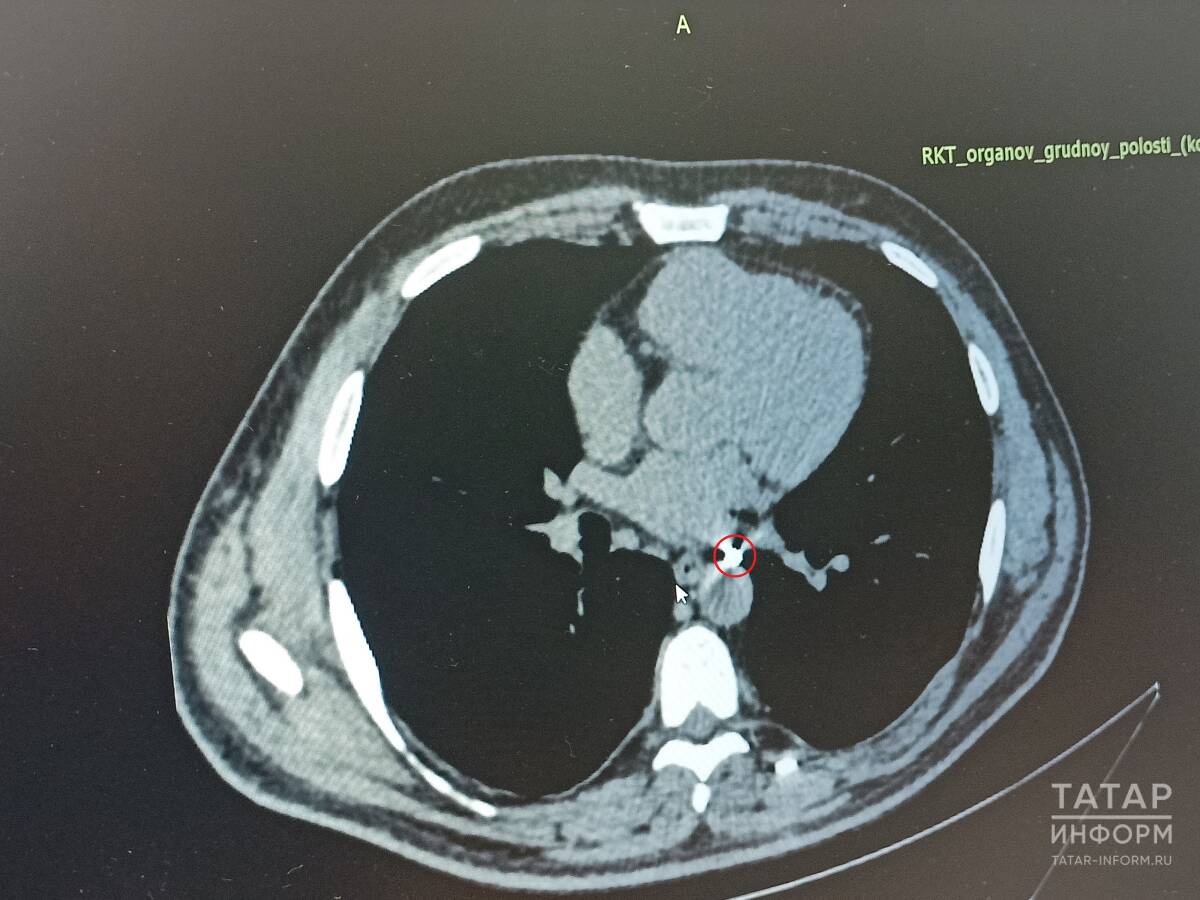

Сложность случая Владимира, объясняют врачи, заключалась в том, что осколок располагался между крупными сосудами – легочной веной и аортой. Учитывая, что ранее он перенес ранение легкого и оно, по словам медиков, приросло к грудной стенке, то сначала необходимо было отделить легкое и только потом доставать осколок.

«В обсуждении ситуации принимали участие руководитель военного госпиталя при РКБ Михаил Бурмистров, торакальные хирурги РКБ и кардиохирурги МКДЦ. Совместно было принято решение оперировать пациента в РКБ», – рассказал заведующий отделением торакальной хирургии №1 РКБ Валерий Матвеев.

Валерий Матвеев: «Осколок располагался на стенке аорты. К счастью, в сам сосуд не проник. Мы успешно удалили его. Сейчас он ничем не угрожал здоровью, но в будущем мог вызвать пролежень и кровотечение»

Операция была выполнена эндоскопически – вместо одного большого разреза медики сделали три прокола по сантиметру. Через один прокол ввели торакоскоп с крохотной видеокамерой на конце, а через остальные – специальные хирургические инструменты.

«Осколок располагался на стенке аорты. К счастью, в сам сосуд не проник. Мы успешно удалили его. Сейчас он ничем не угрожал здоровью, но в будущем мог вызвать пролежень и кровотечение», – подчеркнул врач.